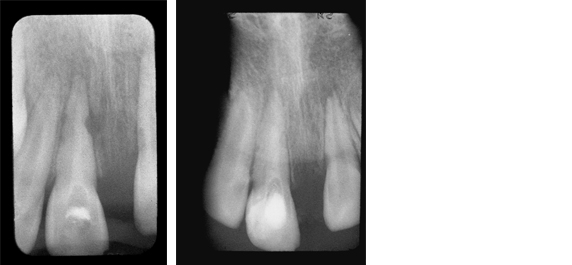

- For complicated cases involving traumatic injury and other instances where extended calcium hydroxide therapy is indicated.

- Treats periapical lesions, abscesses, traumatic injuries, root resorption, root perforations, and weeping canals

- Stimulates apexification and apexogenesis